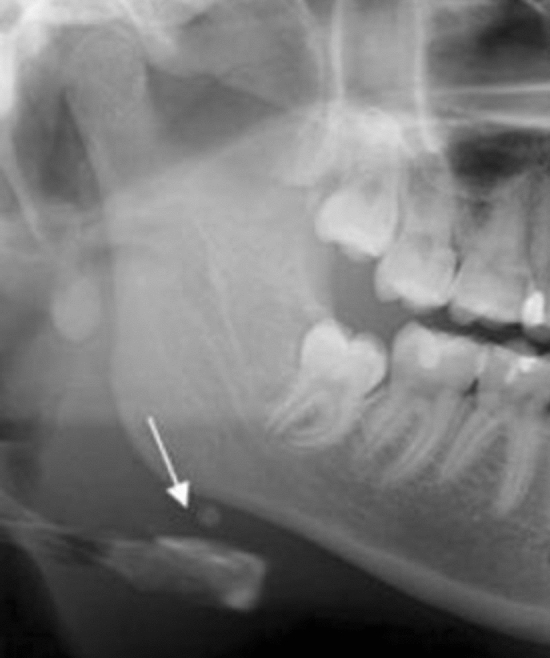

A well-defined, solitary nodular radiopaque structure was seen inferior to the left mandibular border, near the angle. Apart from this, multiple punctuate radiopacities were seen at the level of the lower margin of the cervical vertebra on the left side. Based on the radiographic location and appearance of the lesion on the radiograph, a provisional diagnosis of the left submandibular gland sialolothiasis and carotid artery calcification was made